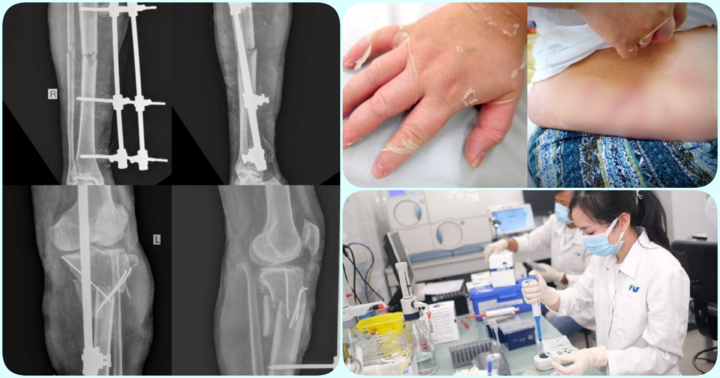

Thời gian gần đây, nhiều bệnh nhân đã phải cấp cứu do lạm dụng corticoid. Dù đã có những cảnh báo về việc lạm dụng corticoid chỉ có hiệu quả trước mắt, nhưng nhiều bệnh nhân vẫn không để tâm dẫn đến những hậu quả nghiêm trọng.